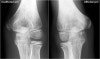

- X-ray

First images of a patient with pain on the medial side, then continue reading.

The medial epicondyle of the affected arm is somewhat more osteopenic. In these cases we usually ask for a comparison view, because it can be very subtle.

The diagnosis is a Little leaguer's elbow which results from chronic stress injury. The lucency on the radiograph, which looks like a widened physis, is due to cartilage ingrowth in the metaphysis.

X-ray : 야구선수 팔꿈치(Little Leaguer’s Elbow)